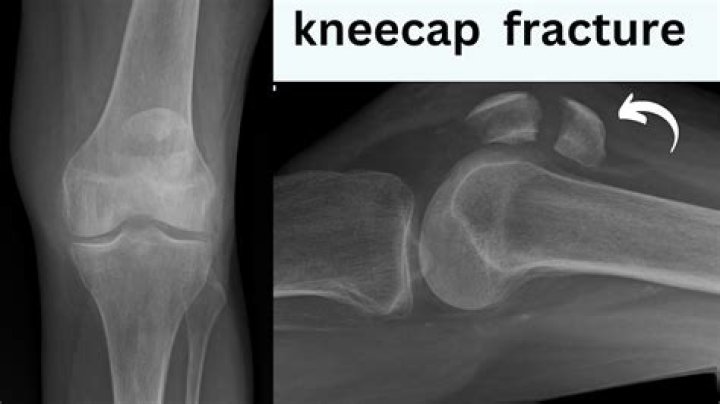

Did i crack my patella?

Can a knee cap crack?

This condition is a crack or fracture of the patella, the bone on the front of the knee that covers the knee joint. The patella helps to protect the joint as well as provide strength and stability. The most common causes of a patella fracture are falls or a sudden, direct blow to the front of the knee.